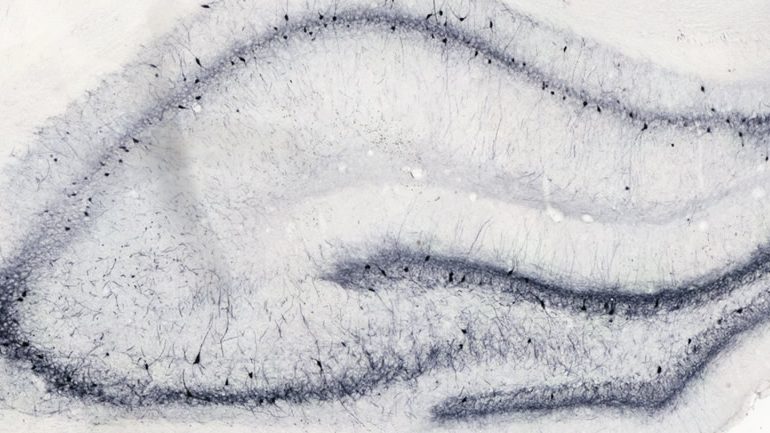

We routinely collect post-mortem samples (e.g. brain and blood) for ex vivo analysis to assess the effect of compounds on relevant biomarkers to understand mechanisms underlying efficacy in the model.